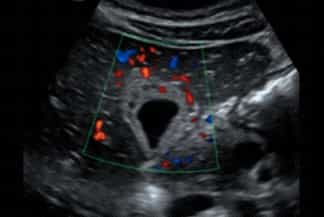

Descrição das figuras: Ultrassonografia de abdome. Vesícula biliar pouco distendida, com importante espessamento parietal, de aspecto estratificado e com aumento de fluxo ao Doppler colorido. Ausência de cálculos. Os achados podem representar colecistite alitiásica.

• Ultrassonografia de abdome: A presença de cálculos na vesícula biliar (colelitíase ) associado a sinal de Murphy ultrassonográfico positivo praticamente define o diagnóstico de colecistite aguda;